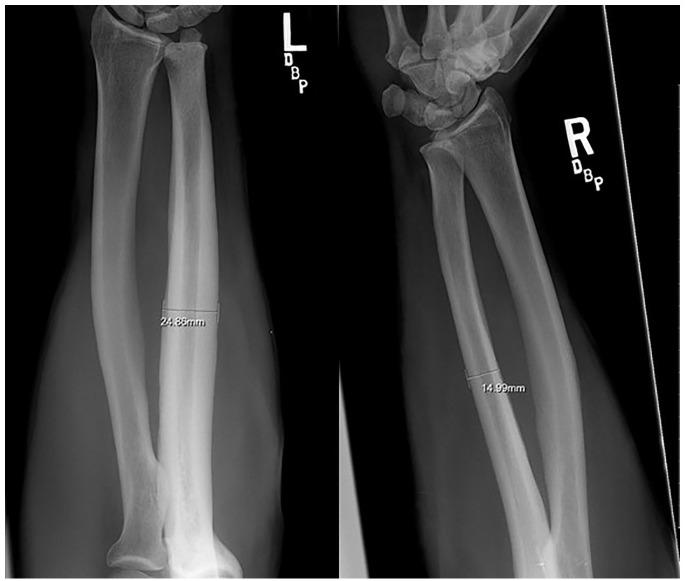

Rodeo bareback riders presented with frequent pain in their grip arm, no radiographic evidence of injury, and clinical signs of peripheral nerve compression. Anteroposterior and lateral X-rays taken for initial evaluation in 17 bareback rodeo athletes were retrospectively reviewed. The diameter of bilateral ulnas was measured at its longitudinal midpoint. Ratio of Ulnar Diameters (grip arm/free arm) and Percentage Diameter Difference were calculated. An independent samples -test was used to assess differences in diameters of grip and non-grip arms.

RESULT

The mean ulnar diameter was 18.4 ± 3.5 in the grip arm and 16.6 ± 3.5 in the non-grip arm ( < 0.001). The mean ratio of grip to free arm ulnar diameter was 1.42 ± 0.21 (range = 1.05-1.92). The mean diameter percent difference measured 42.3% (range = 4.7%-92.0%), and the grip arm was observed to have a greater ulnar diameter compared to the non-grip arm.

骑无鞍马的牛仔竞技运动员出现握力臂频繁疼痛,无影像学损伤证据,且有周围神经受压的临床体征。对17名骑无鞍马的牛仔竞技运动员进行初步评估时拍摄的前后位和侧位X线片进行回顾性分析。在双侧尺骨的纵向中点测量其直径。计算尺骨直径比(握力臂/非握力臂)和直径百分比差异。采用独立样本t检验评估握力臂和非握力臂直径的差异。

结果

握力臂的平均尺骨直径为18.4±3.5,非握力臂为16.6±3.5(<0.001)。握力臂与非握力臂尺骨直径的平均比值为1.42±0.21(范围=1.05 - 1.92)。平均直径百分比差异为42.3%(范围=4.7% - 92.0%),观察到握力臂的尺骨直径大于非握力臂。